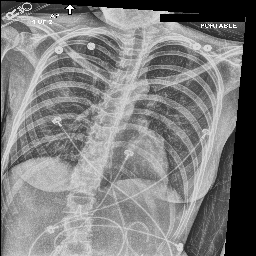

Evaluation of Generated Reports

Ground Truth TieNet Ours (full)

[Uncaptioned image] cardiomegaly is moderate. bibasilar atelectasis is mild. there is no pneumothorax. a lower cervical spinal fusion is partially visualized. healed right rib fractures are incidentally noted. ap portable upright view of the chest. there is no focal consolidation, effusion, or pneumothorax. the cardiomediastinal silhouette is normal. imaged osseous structures are intact. pa and lateral views of the chest. there is mild enlargement of the cardiac silhouette. there is no pleural effusion or pneumothorax. there is no acute osseous abnormalities.

[Uncaptioned image] as compared to the previous radiograph, the monitoring and support devices are unchanged. unchanged bilateral pleural effusions, with a tendency to increase, and resultant areas of atelectasis. the air collection in the bilateral soft tissues is slightly decreased. unchanged right picc line. no definite evidence of pneumothorax. as compared to the previous radiograph, the patient has received a nasogastric tube. the course of the tube is unremarkable, the tip of the tube projects over the middle parts of the stomach. there is no evidence of complication, notably no pneumothorax. the other monitoring and support devices are constant. constant appearance of the cardiac silhouette and of the lung parenchyma. as compared to the previous radiograph, there is no relevant change. tracheostomy tube is in place. there is a layering pleural effusions. NAME bilateral pleural effusion and compressive atelectasis at the right base. there is no pneumothorax.

[Uncaptioned image] the course of the dobbhoff feeding catheter is unremarkable, and its tip is seen projecting over the stomach. there is no evidence of complications, specifically no pneumothorax. as compared to the prior radiograph dated DATE, there has been no other significant interval change. ap portable upright view of the chest. overlying ekg leads are present. there is no focal consolidation, effusion, or pneumothorax. the cardiomediastinal silhouette is normal. imaged osseous structures are intact. as compared to the previous radiograph, there is no relevant change. the endotracheal tube terminates approximately 3 cm above the NAME. the endotracheal tube extends into the stomach. there is no evidence of complications, notably no pneumothorax. there is no pleural effusion or pneumothorax.

[Uncaptioned image] interval placement of a left basilar pigtail chest tube with improving aeration in the left mid to lower lung and near complete resolution of the pleural effusion. there are residual patchy opacities within the left mid and lower lung as well as at the right base favoring resolving atelectasis. no pneumothorax is appreciated on this semi upright study. heart remains stably enlarged. mediastinal contours are stably widened, although this NAME be related to portable technique and positioning. this can be better evaluated on followup imaging. no pulmonary edema. as compared to the previous radiograph, the patient has been extubated. the nasogastric tube is in unchanged position. the lung volumes remain low. moderate cardiomegaly with minimal fluid overload but no overt pulmonary edema. no larger pleural effusions. no pneumonia. ap upright and lateral views of the chest. there is moderate cardiomegaly. there is no pleural effusion or pneumothorax. there is no acute osseous abnormalities.

Table 4: Sample images along with ground truth and generated reports. Note that upper case tokens are results of anonymization.

Table 4 demonstrates the qualitative results of our full model. In general, our models are able to generate descriptions that align with the logical flow of reports written by radiologists, which start from general information (such as views, previous comparison), positive, then negative findings, with the order of lung, heart, pleura, and others. TieNet also generates report descriptions with such logical flow but in slightly different orders. For the negative findings cases, both our model and TieNet do well on generating reasonable descriptions without significant errors. Regarding the cases with positive findings, TieNet and our full model both cannot identify all radiological findings. Our full model is able to identify the major finding in each demonstrated case. For example, cardiomegaly in the first case, pleural effusion, and atelectasis in the second case.

A formerly practicing clinician co-author reviewed a larger subset of our generated reports manually. They drew several conclusions. First, our full model tends to generate sentences related to pleural effusion, atelectasis, and cardiomegaly correctly—which is aligned with the clinical finding scores in Table 3. TieNet instead misses some positive findings in such cases. Second, there are significant issues in all generated reports, regardless of the source model, which include the description of supportive lines and tubes, as well as lung lesions. For example, TieNet is prone to generate nasogastric tube mentions while our model tends to mention tracheostomy or endotracheal tube, and yet both models have difficulty identifying some specific lines such as chest tube or PICC line. Similarly, both systems do not generate the sentence with positive lung parenchymal findings correctly.

From this (small) sample, we are unable to draw a conclusion whether our model or TieNet truly outperforms the other since both present with significant issues and each has strengths the other lacks. Critically, neither of them can describe the majority of the findings in the chest radiograph well, especially for positive cases, even if the quantitative metrics demonstrate the reasonable performance of the models. This illustrates that significant progress is still needed in this domain, perhaps building on the directions we explore here before these techniques could be deployed in a clinical environment.